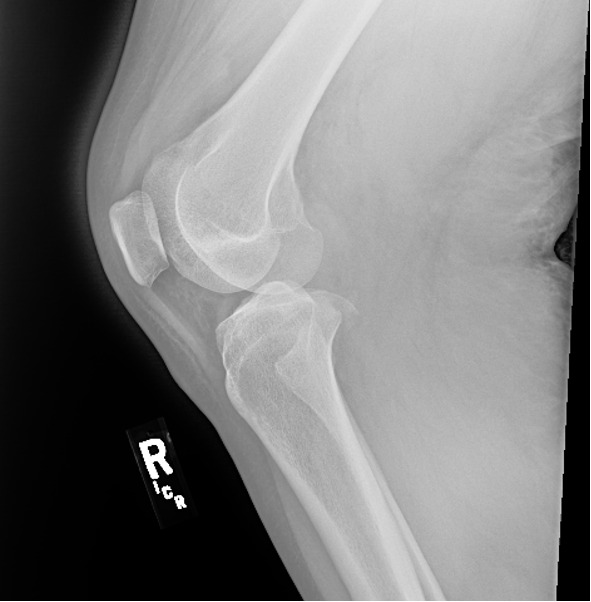

An 18-year-old male with a past medical history significant for Down’s syndrome, morbid obesity, and dilated cardiomyopathy status septal myomectomy on 75mg metoprolol daily, presented to the ED via Emergency Medical Services (EMS) after a mechanical fall at home. The patient was walking outside when he tripped and landed with full weight on his right knee. (Figure 1) He was unable to brace himself. He denied a loss of consciousness but reported right knee pain and inability to ambulate. EMS noted a right lower extremity deformity and pedal pulses were present. Upon arrival to the ED, the patient was noted to have a mottled, cool limb with absent pedal pulses. (Figure 2) The patient was immediately upgraded to a Level 1 trauma alert and taken into the trauma bay. He was placed on a cardiac monitor and noted to have sinus tachycardia sustained in the 160s. On examination, he was diaphoretic but alert and oriented. He could not range the right knee, ankle, or toes. The popliteal fossa and posterior aspect of the right lower extremity was indurated and tender to palpation.

A quick portable knee x-ray demonstrated a right medial tibial plateau fracture with a displaced fragment measuring approximately 1.2 x 1.6 cm on the frontal view. (Figures 5 and 6) It was determined that the patient likely had dislocated his knee, resulting in significant vascular injury to the popliteal artery. Vascular surgery and orthopedics were consulted, and the patient was taken immediately to the operating room for revascularization and exploration.